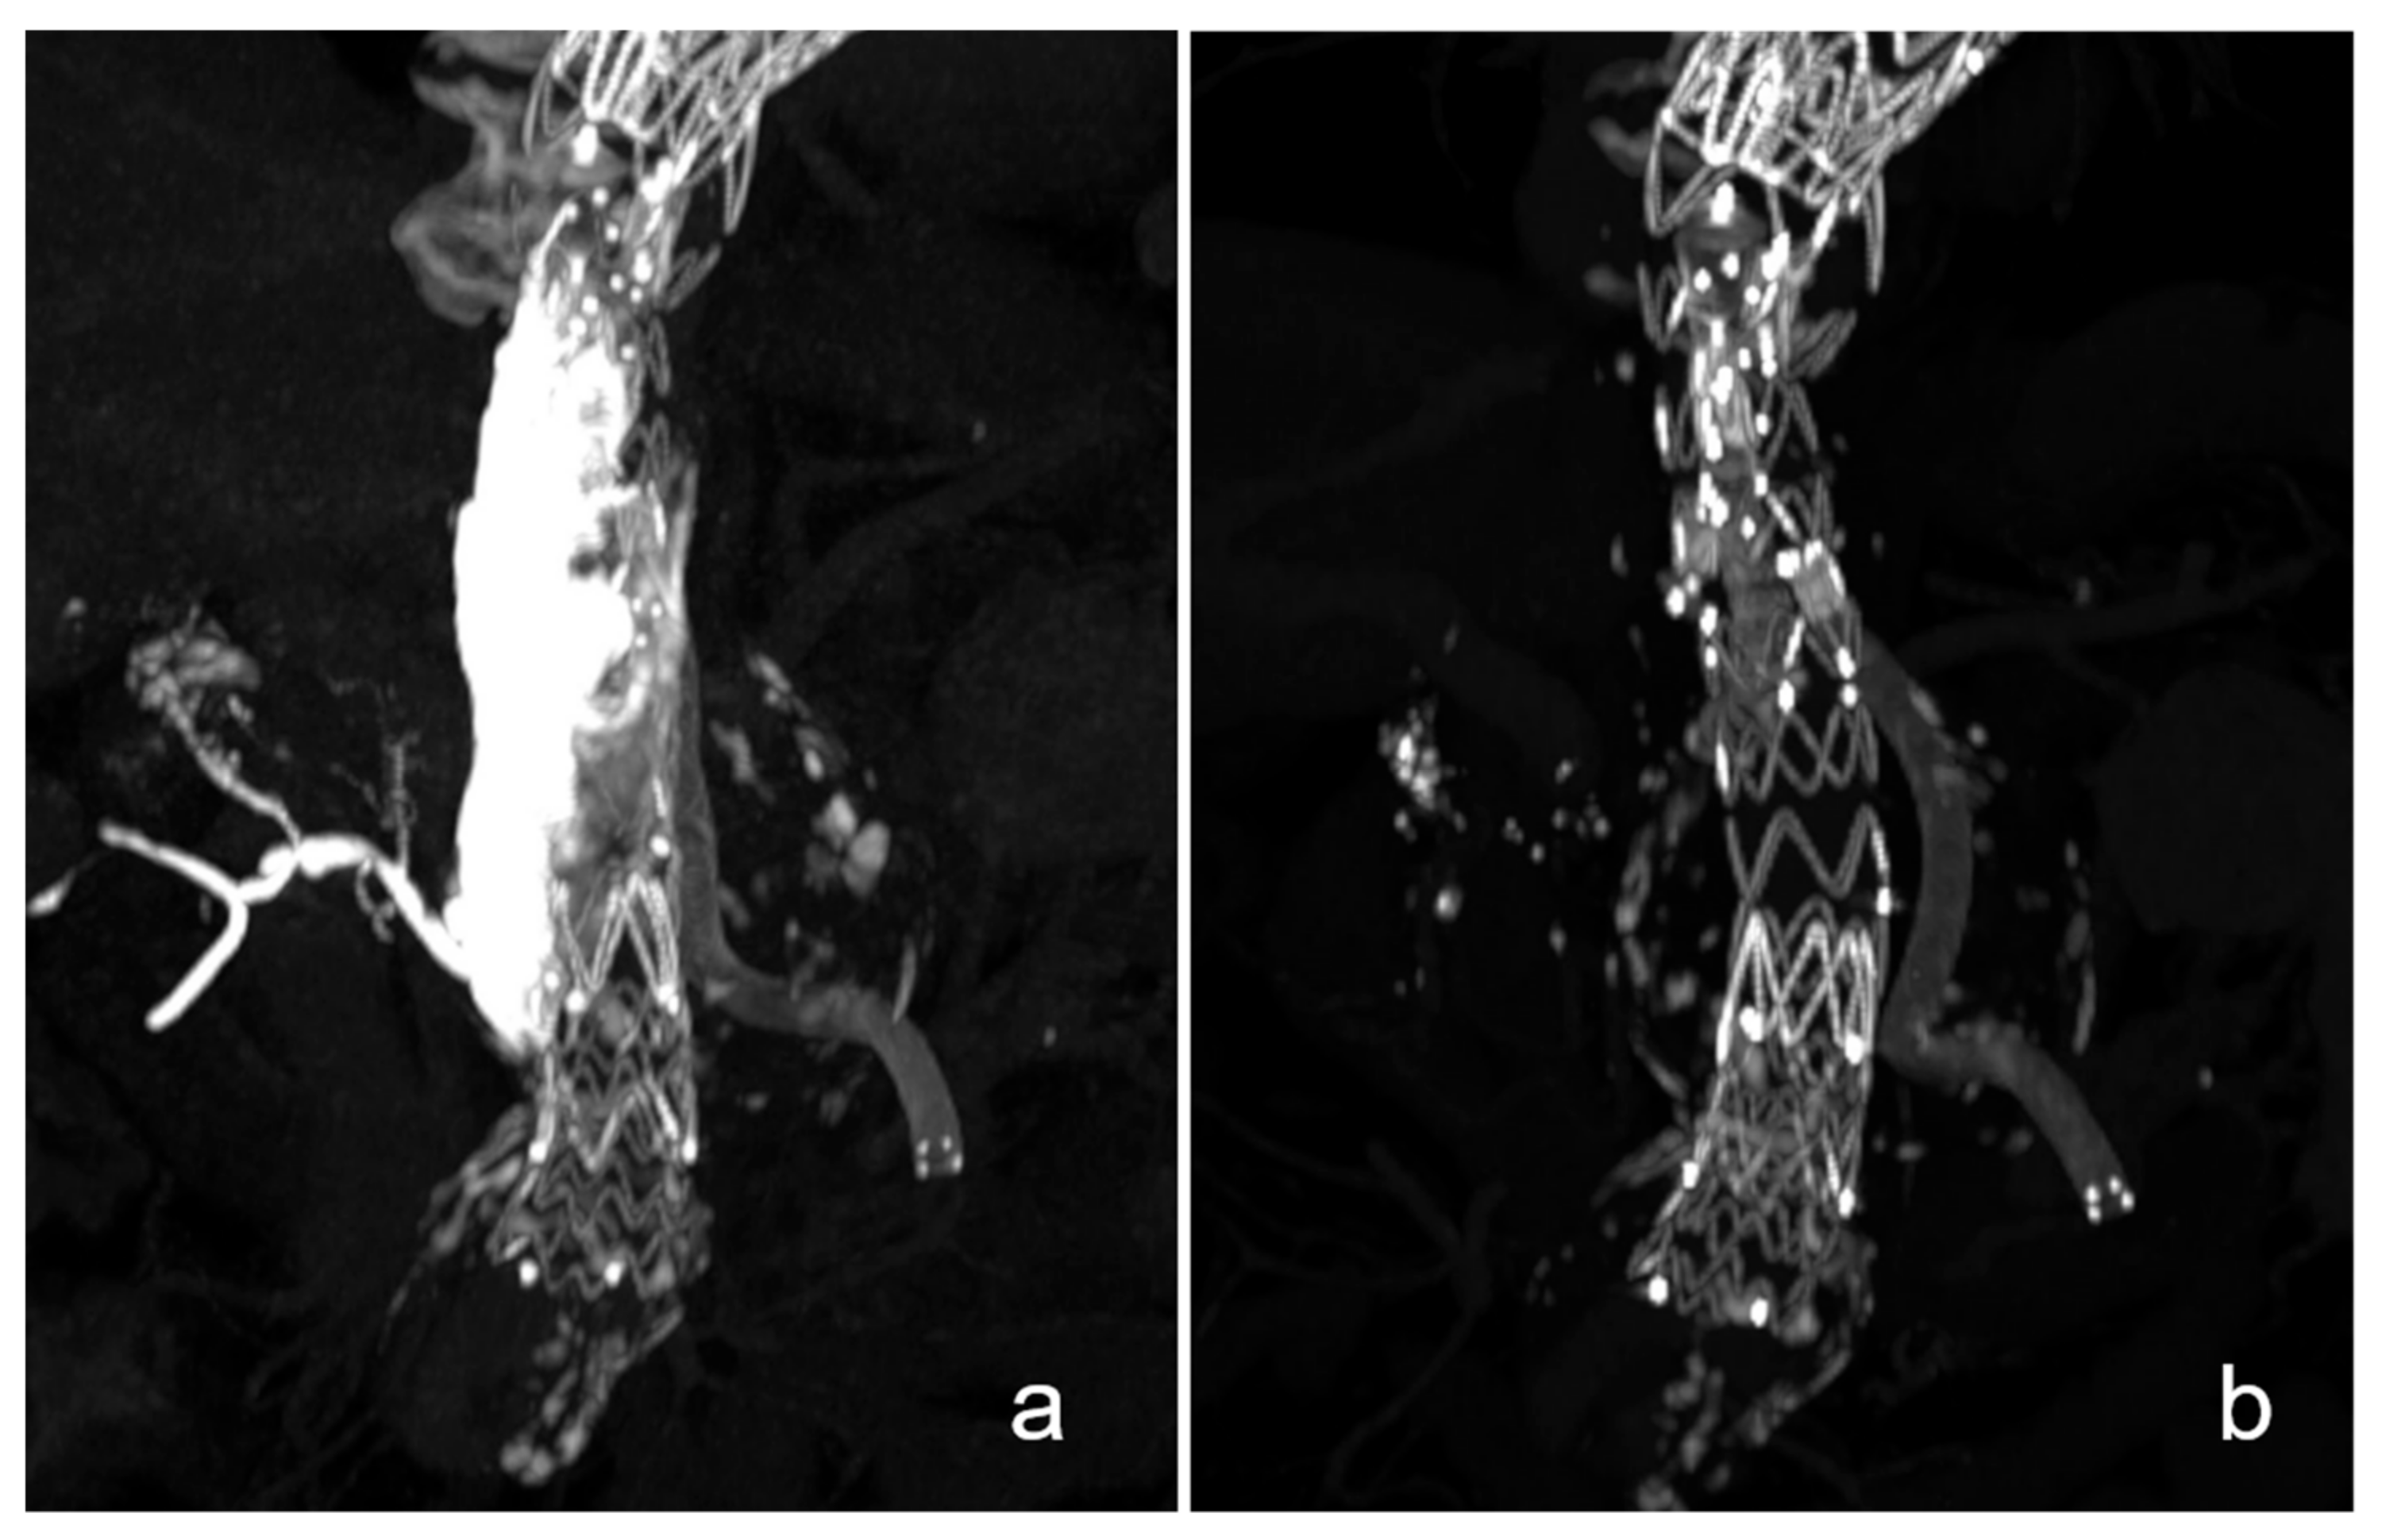

Dissolution of the NBCA cast 36 months after unilateral repair of the left iliac artery.

Aneurysmal rupture of the common left iliac artery in this patient was treated by implanting a covered stent graft with add-on NBCA embolization of the aneurysm rupture site. In the postinterventional scan, the NBCA cast is clearly visible (a). After 3 years, most of the cast has almost fully dissolved (b).